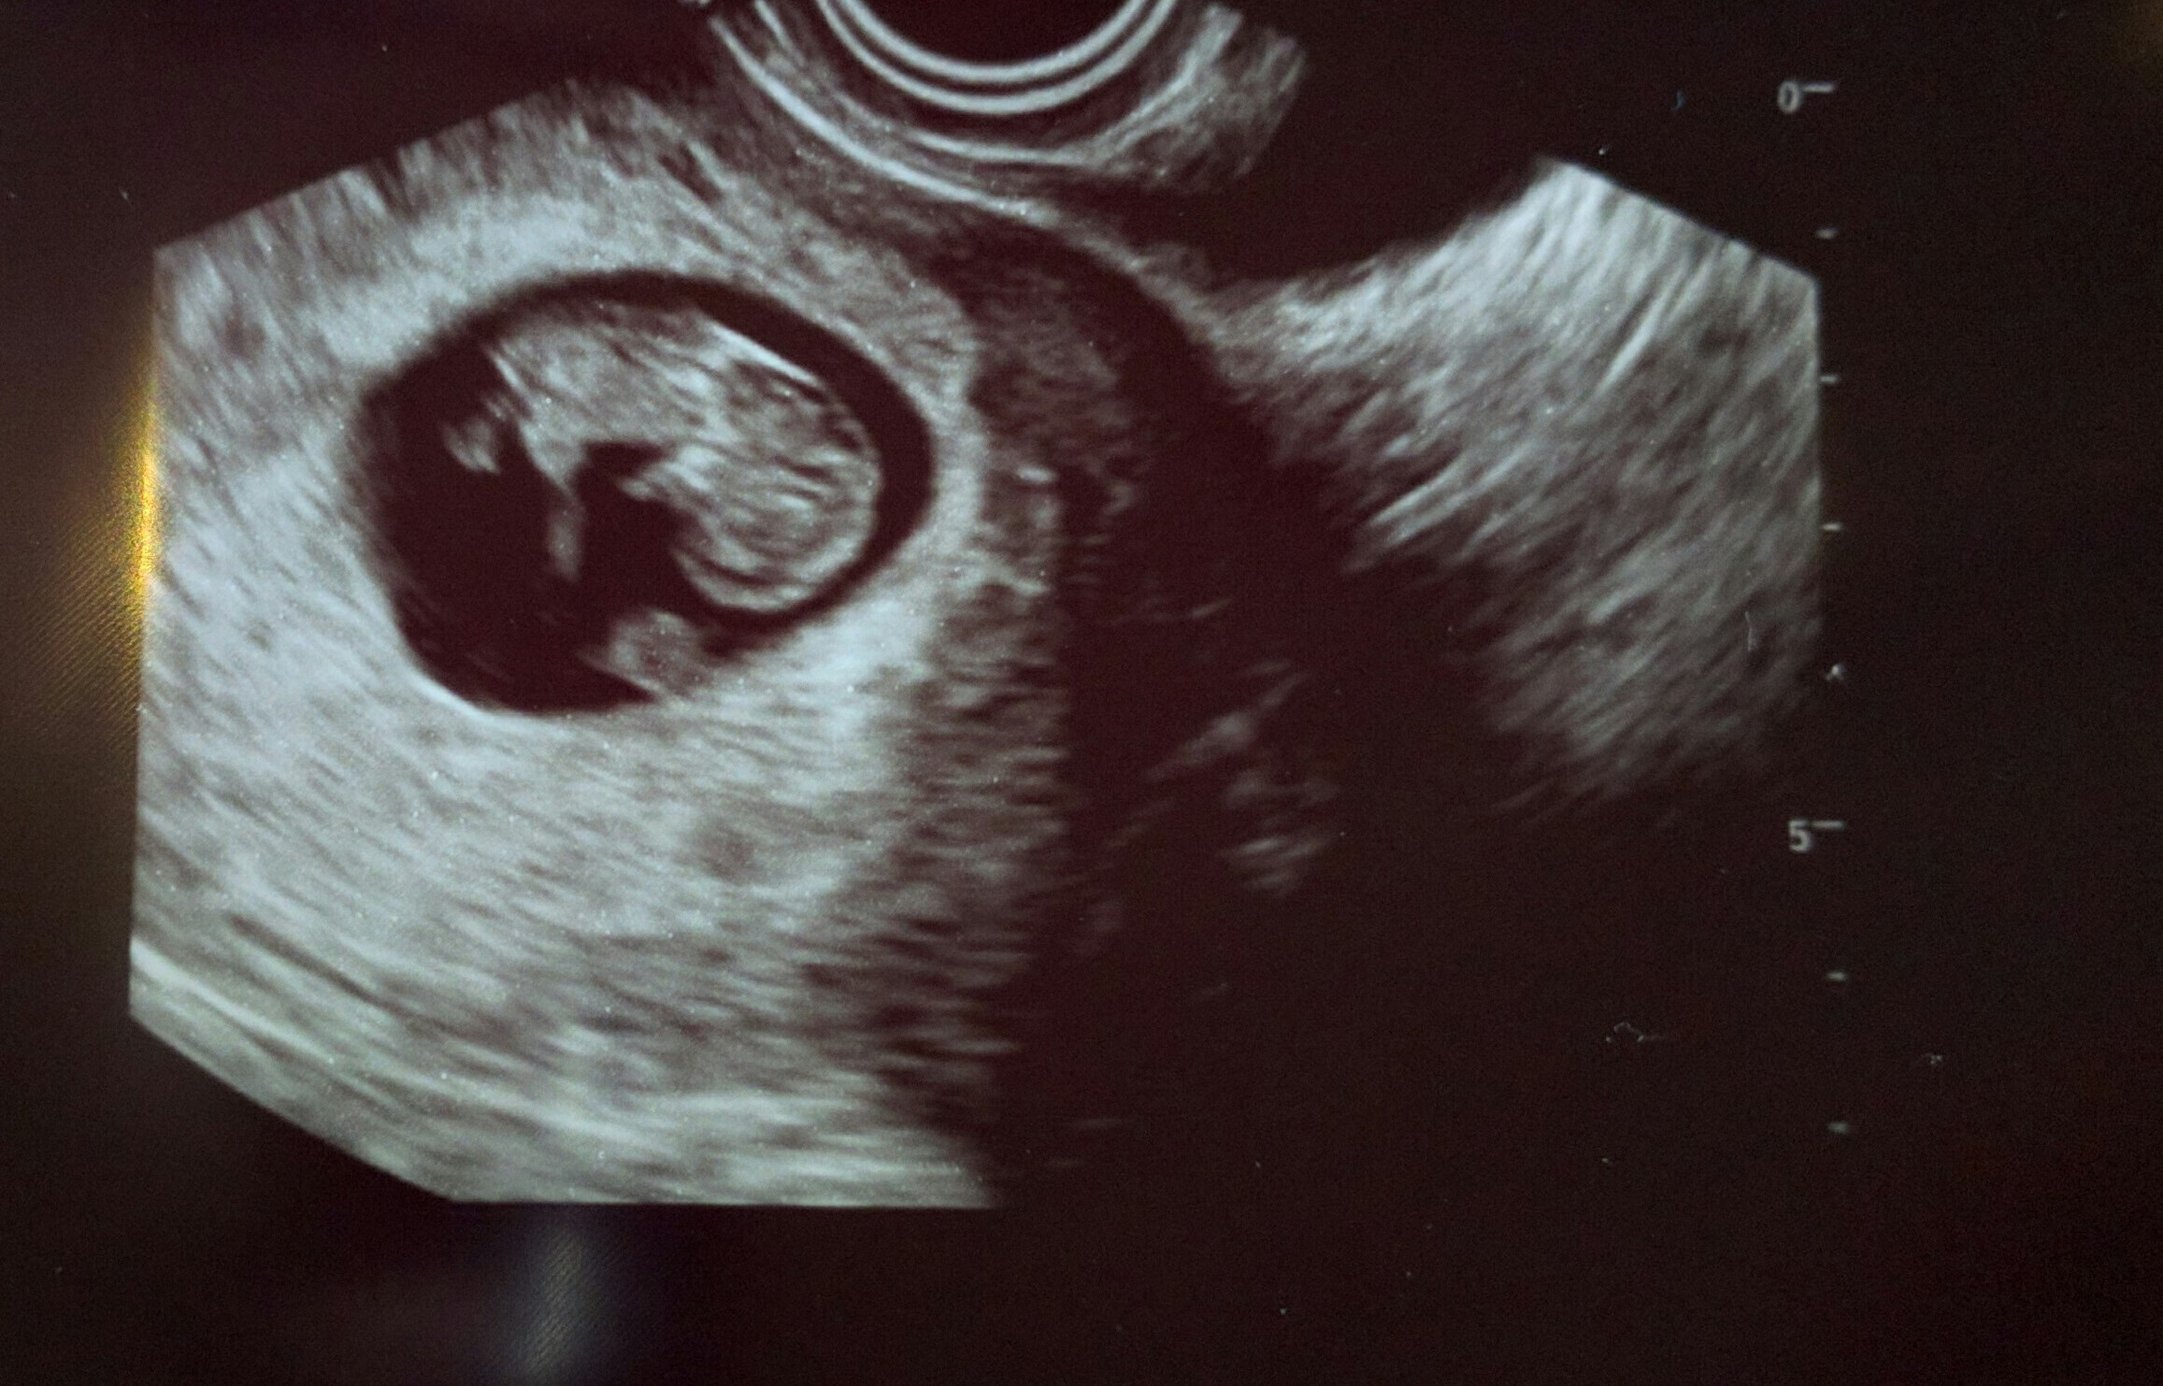

Our little baby!! 12 weeks 4 days and actually looking like a baby now it was so fun getting to watch it move around! This is my first pregnancy and due date is September 3rd!